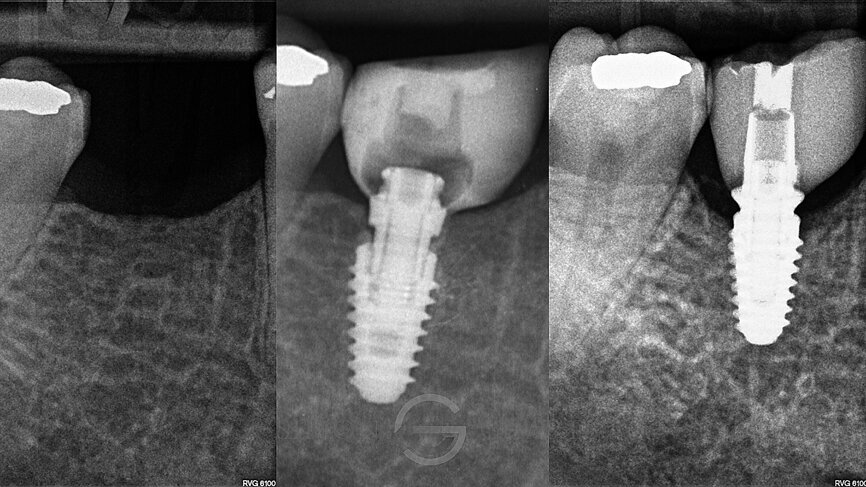

Following a discussion of the options for replacement of LR6, the patient elected for an implant-retained solution. A MegaGen AnyRidge 4 x 10 mm implant was placed utilising a surgical guide for position of the pilot hole. An immediate temporary crown was fabricated using the MegaGen fuse abutment and DMG Luxatemp. A silicone index of the diagnostic wax-up was fabricated and the temporary crown was polished and taken out of occlusion while the implant fully integrated (Fig. 3).

Following 3 months of integration, the patient attended the practice for the restoration of the implant with a definitive crown. During this period, the soft tissue had been given time to mature and a beautiful molar soft tissue profile had formed (Figs. 4 & 5).